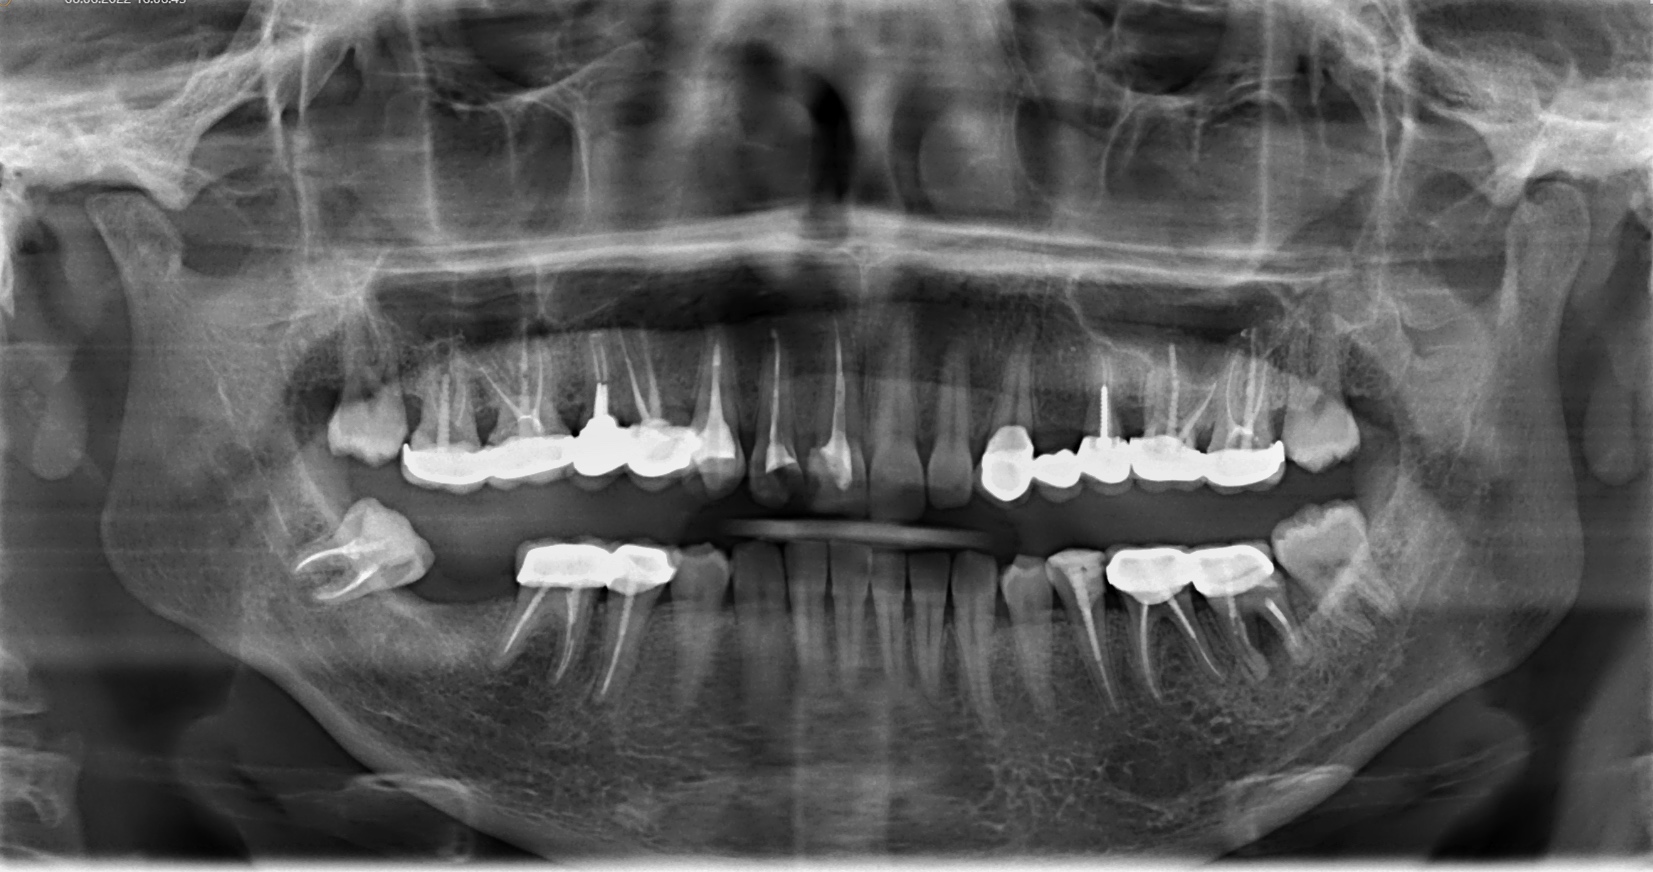

1. Есть ли на снимке признаки воспаления в области верхушек корней зубов?

2. Наблюдаются ли ретенированные или дистопированные зубы?

3. Каково состояние костной ткани вокруг зубов — есть ли признаки резорбции или кисты?

4. Присутствуют ли патологические изменения в височно-нижнечелюстном суставе?